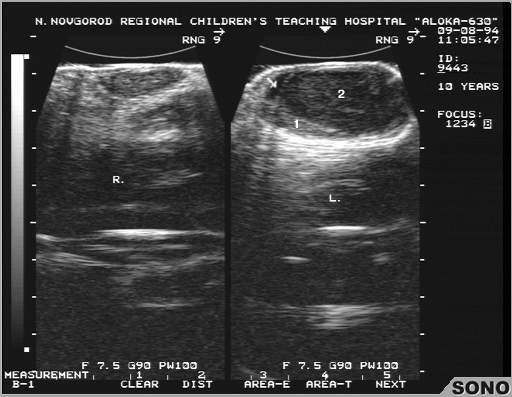

Острый орхит